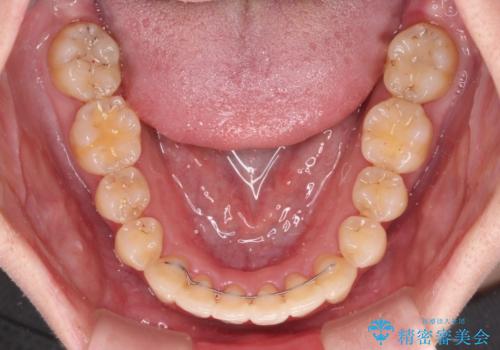

上下前歯のデコボコをきれいに インビザラインによる矯正治療

ワイヤー矯正を併用したことで前歯の叢生を速やかに解消することができました。

一方口元の突出感を改善するために時間がかかり、2年超を要しましたが、満足のいく仕上がりとなりました。